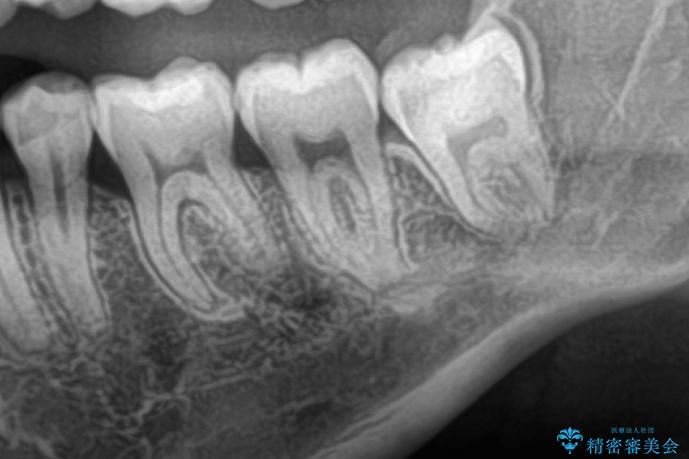

- 親知らずを抜きたいとのことで来院された患者様です。

CTで神経の位置などを確認し、抜歯術を行いました。

しっかり麻酔が効いたことを確認してから安全に抜歯を行いました。